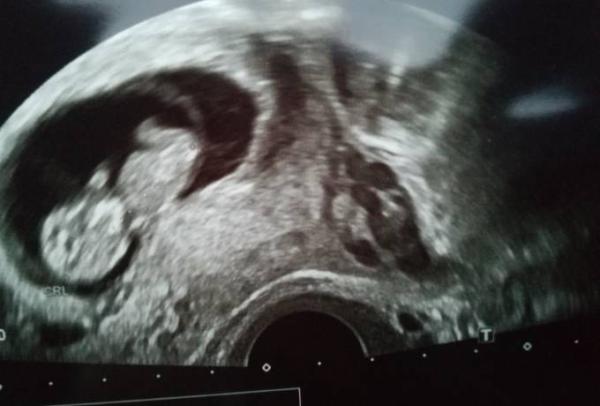

So war eben mal wieder Frauenarzt. Heute gab es mutterpass und ein schönes Bild alles ist super

Ja bin super erleichtert. Am 11 Januar endlich mal kein 2 wochen Rhythmus mehr das kleine ist 3,25 cm und das ist 10+1 bin 10+0 also alles im Rahmen

Ach wie schön! Tolles Bild, tolle Maße!